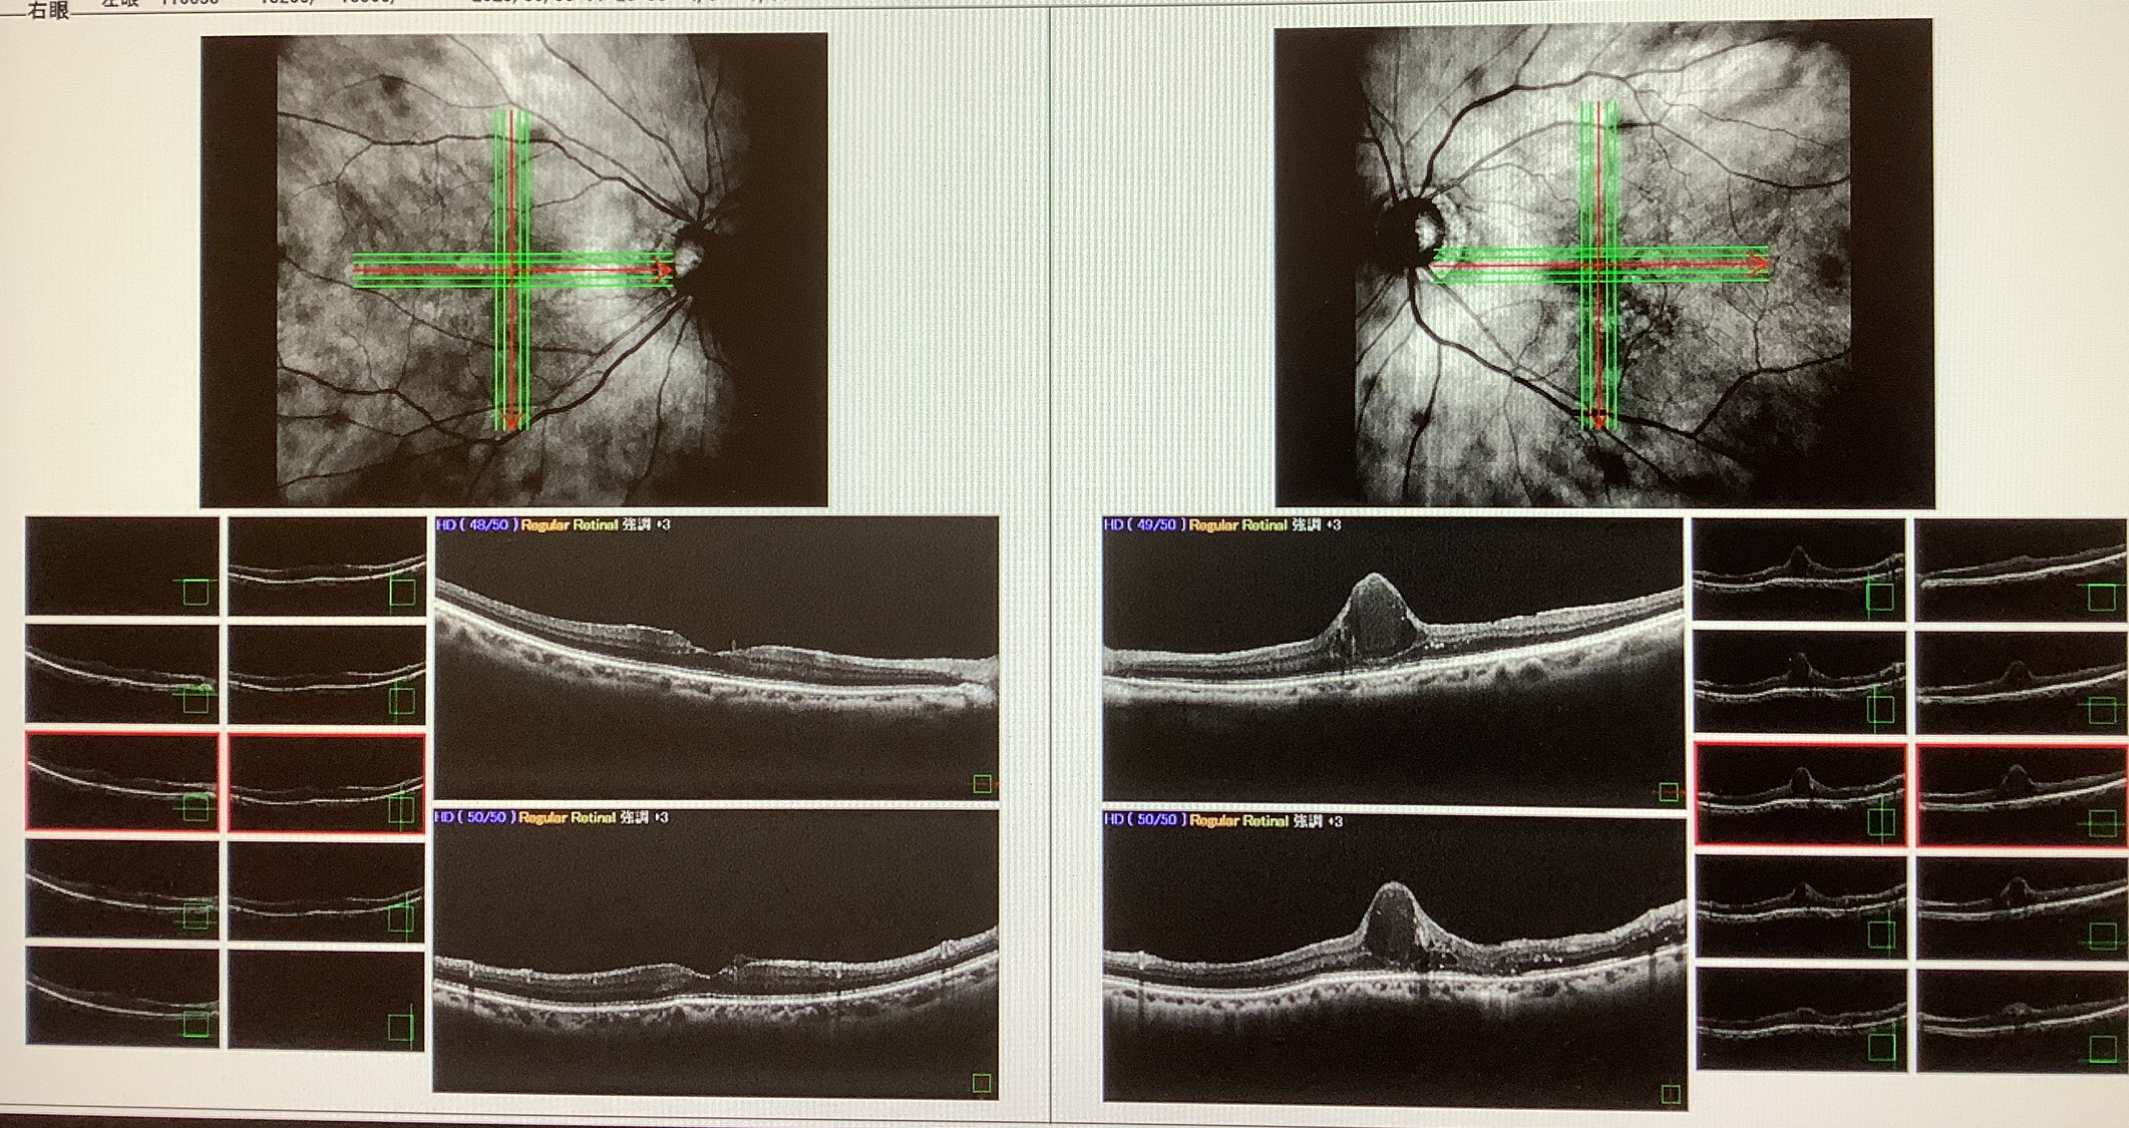

今日の外来では先週の水曜日に黄斑浮腫で硝子体手術を受けていただいた80代の女性の方の経過観察の診察がありました。元々、左眼の網膜静脈閉塞症があり、黄斑上膜に対して6年ほど前に左眼の硝子体手術を行ったのですが、術後3か月くらいで黄斑浮腫が出てきてしまい、抗VEGF薬の硝子体注射、ステロイドのテノン下注射、レーザー治療を繰り返し行いましたが、黄斑浮腫はなかなか頑固で改善に乏しく、今回、2度目の手術をすることとなりました。

OCT検査上、黄斑部に浮腫が塊り(cyst)として存在していそうだったので、そのcystを取り除く処置を行いました。黄斑に限らず、体のどこかに嚢胞ができる病気はありますが、袋状の構造ができてしまい、そこに液体の成分が貯留してしまうため、何らかの処置で水を抜くだけだと、一時的にはよくなっても、またその袋の中に水が溜まってしまい、元に戻ってしまうので、その袋を取ってみようと思いました。黄斑浮腫に対しての、このような手術はcystectomy(システクトミー)と呼ばれ、うまくいけば、浮腫は治り視力もある程度の回復も期待できますが、あくまで黄斑の水溜まりを取る手術ですから、網膜の細胞が悪くなってしまっていれば、なかなか視力が改善するものでもありません。なので、視力をよくしたいと期待して受ける手術ではなく、抗VEGF治療をしてもすぐ浮腫が出てしまって、注射以外の方法で浮腫を起こさないようにするためであり、視力の回復はプラスαの目的になるかと思います。もともと抗VEGF治療をして黄斑浮腫が引いても視力が改善しない人は、黄斑の細胞が悪くなってしまっていると思われますので、システクトミーで浮腫が起こらなくなったとしても、視力の改善は期待できないかと思います。また、視機能に大事な黄斑部に対して操作をするので、思わぬ悪影響で視力が下がる恐れもある手術だと思います。

今回の患者さんも手術の時に空気を入れた影響もまだあるので、術前よりは視力も下がっていますが、OCT検査ではあれだけ頑固な黄斑浮腫がきれいになくなっていて、手術自体はうまくいっていると思えました。